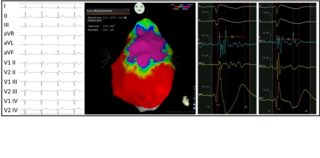

Through the use of dedicated software that is associated with mapping systems, it is possible to reconstruct the three-dimensional geometry of the heart and to identify with precision the areas of myocardium affected by the disease (figure 2).

To achieve this goal, it is necessary to administer ajmaline during this mapping phase. This drug is able to unmask the cardiac electrical anomalies to the maximal degree, enabling the visualization and pronounced definition of the area of anomalous substrate to be treated.

Once the anomalous electrical substrate has been identified, it is possible to perform the ablation of this area. Radiofrequency disbursements are rapid and precise, in order to limit ablation to only the outer surface of the heart, enabling the elimination of only surface cells (figure 3).

The purpose of the ablation is to eliminate all the anomalous electric potentials located on the epicardium (figure 4), resulting in a complete normalization of the electrocardiogram which no longer shows, after ablation, the classical electrical anomalies of BrS (figure 5). These elements are also associated with the disappearance of malignant ventricular arrhythmias in post-ablation follow-up.